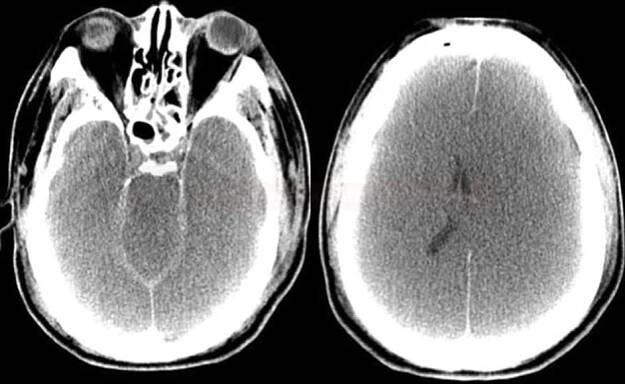

Difúzní edém mozku v důsledku hypoperfúze během operace v ECC

Otok mozku (mozkový edém) je specifickým otokem části těla. Ostatní oteklé orgány či tkáně se mohou relativně volně zvětšit, mozek je však uzavřen v lebce, a proto je jeho otok spojen s nebezpečným zvýšením nitrolebního tlaku.

Co je to otok mozku?Otok mozku je stav, kdy mozková tkáň kvůli nahromaděné tekutině zvýší svůj objem. Intrakraniální tlak pak způsobuje zhoršení průtoku krve, což má za následek, že mozek není dostatečně okysličován. V důsledku tohoto stavu může dojít k poškození či odumření mozkových buněk.